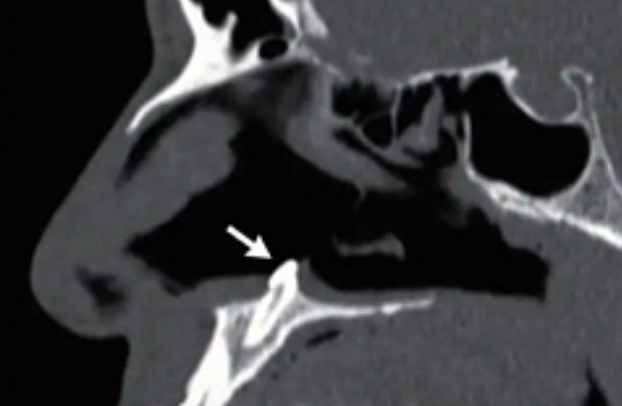

Фото: The New England Journal of Medicine

Британец обратился к врачам за помощью: он не мог дышать. Врачи провели обследование и выяснили, что у пациента в носу растет зуб. Медики диагностировали у мужчины искривление перегородки и начали расспрашивать британца, не получал ли он когда-нибудь травмы носа.

Мужчина заявил, что никогда не ломал нос. Так, врачи поняли, что зуб просто рос в неположенном месте — это аномалия. Дефект может быть проявлением врожденного порока, передает Daily Star.

Зуб оказался около 1,4 сантиметра в длину. Его удалили. Сообщается, что проблемы с дыханием у пациента прошли.